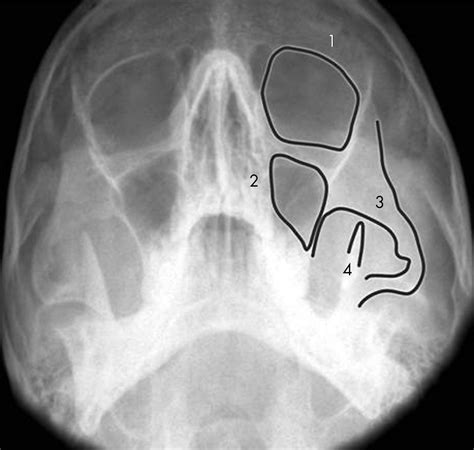

The zygomatic arches are part of the facial skeleton and are formed by the zygomatic bones. These bones connect to the temporal bones and the maxilla, creating a framework that supports the facial muscles and soft tissues. The zygomatic arches are critical for facial aesthetics and function, making their assessment through imaging techniques like the Smv Zygomatic Arches Xray indispensable.

Interpreting the results of a Smv Zygomatic Arches Xray requires expertise in radiology. The radiologist looks for various indicators, including:

• Fractures: Visible breaks or displacements in the zygomatic arches.

• Tumors: Abnormal masses or growths that may affect the bone structure.

• Anomalies: Congenital or developmental issues that alter the normal anatomy of the zygomatic arches.

• Soft Tissue Involvement: Any signs of soft tissue damage or inflammation that may be associated with the zygomatic arches.